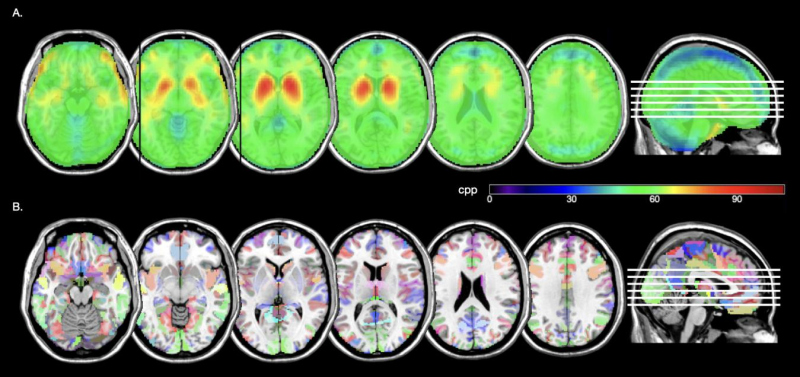

Además, se creó una imagen promediada de todas las imágenes de SPECT con 99mTc-TRODAT-1 de la muestra seleccionada y se sobrepuso con una imagen anatómica cerebral (RM en secuencia T1) en el espacio estandarizado de manera que se puede observar la captación del radiofármaco en los núcleos basales, en diferentes cortes axiales (Fig. 3).